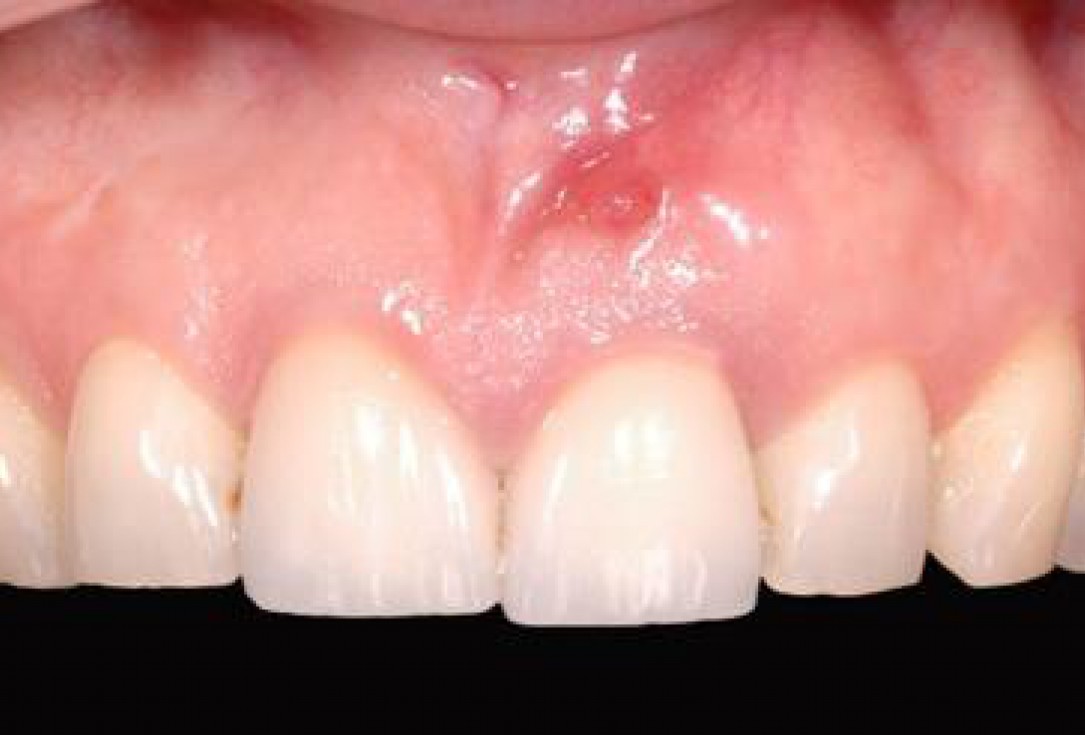

1/18 - Longitudinal fracture on the root resected tooth 21 with visible buccal fistulaGBR together with soft tissue augmentation with mucoderm® and maxresorb® - Dr. S. Scherg

Longitudinal fracture on the root resected tooth 21 with visible buccal fistula